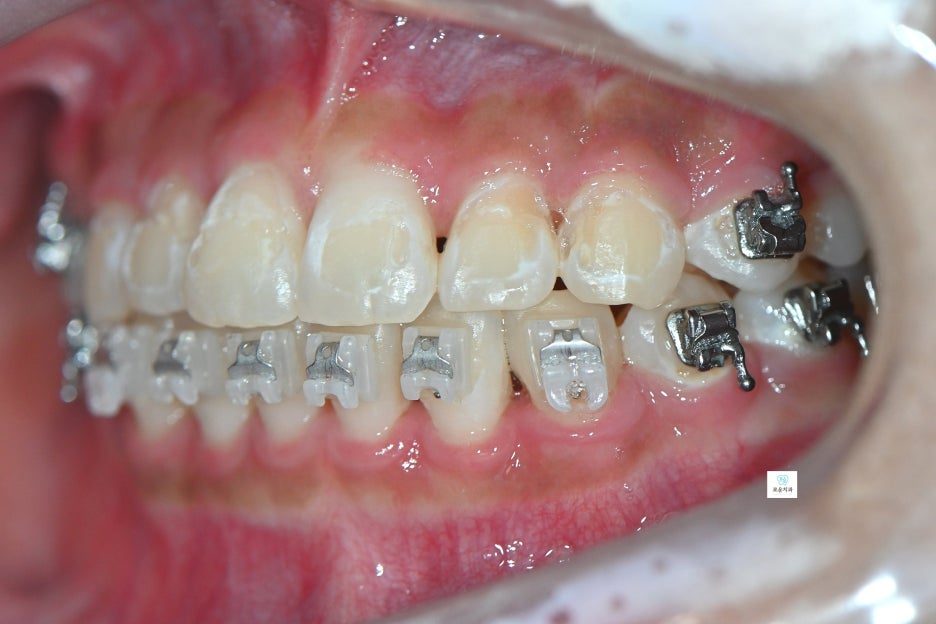

자연스럽고 깔끔하게 마무리된

앞니 치료 결과를 확인할 수 있습니다.